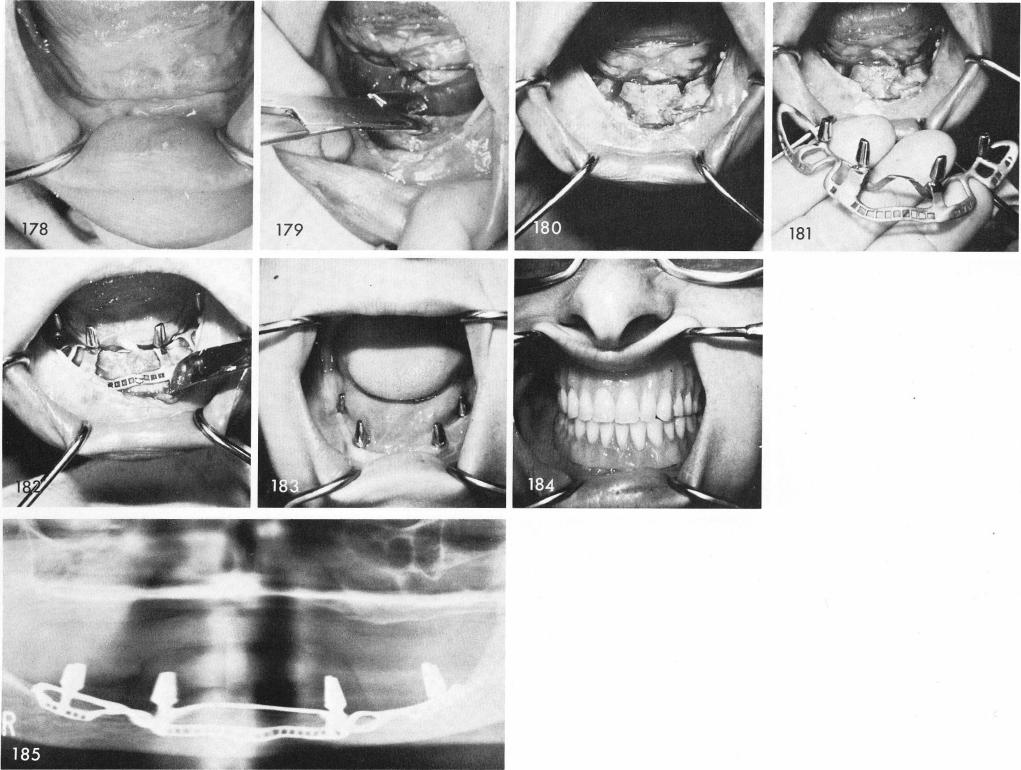

When it is determined that a knife edge ridge exists beneath the soft tissues, fig. 178, a bone rongeur is sometimes used to remove it, fig. 179. In these situations where alveolar bone still exists anteriorly cross over struts made deep into the bone to its denser basal portion are made, fig. 180, to support the struts of the implant that support the anterior posts, figs. 181, 182. Healing in these situations also is usually excellent, fig. 183, and the denture is completed. Fig. 184 shows accuracy of the fit. Final x-ray, fig. 185.

1 Clinical view of mandible with knife edge ridge